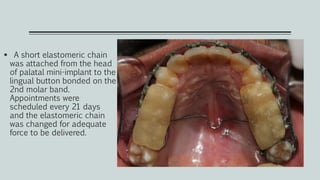

 A short elastomeric chain

was attached from the head

of palatal mini-implant to the

lingual button bonded on the

2nd molar band.

Appointments were

scheduled every 21 days

and the elastomeric chain

was changed for adequate

force to be delivered.

 The correction of scissor bite was achieved within a span of three and a

half months.